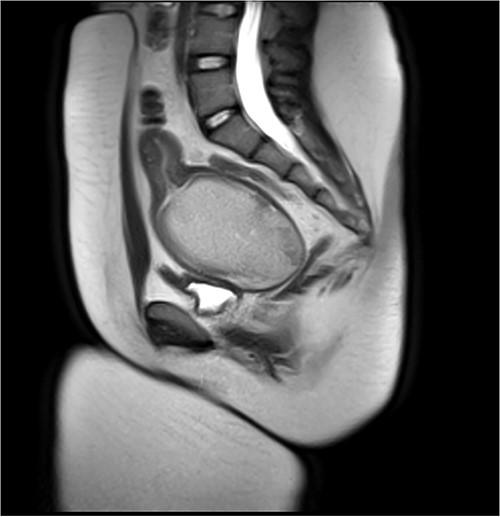

A 13-year-old female presented to the emergency department for increasingly severe chronic cyclic abdominal. She reported thelarche and pubarche at age 11 but had not reached menarche. Physical exam was significant for general abdominal tenderness and firm abdominal mass. External genitalia were notable for a normal hymen but no vaginal opening or bulge. On rectal exam, a firm mass was palpated ~4 cm proximal to anal opening. Imaging confirmed HMC with distension of the proximal vagina measuring 9.9 cm in its greatest dimension. The area of vaginal agenesis was ~5 cm from distal end of HMC to the perineum (Fig. 1).

Pre-vaginoplasty MRI- Image was taken after IR drainage and suppression to allow distension pre-vaginoplasty.